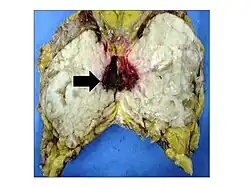

Gross image of an excised phyllodes tumor.

Malignant phyllodes tumors can behave similarly to sarcomas leading to development of blood-borne metastases.[16] Approximately 10% of phyllodes tumor develop distant metastases and this occurrence is higher (20%) in patients with histological-identified malignant tumors.[16] The most common site for distant metastases include the lung, bone, and abdominal viscera.[17] In more insidious cases, the parotid region has also been described in literature.[18]